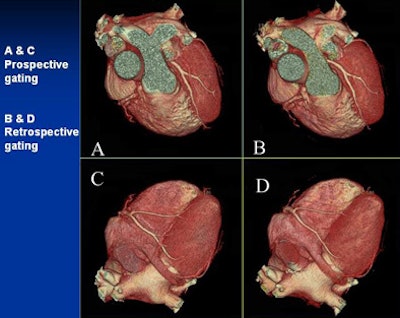

![]() |

| Can you tell the difference between the low-dose prospectively gated and and higher-dose retrospectively gated coronary CTA images above and below? The acquisition method for each image is marked. |

Keep in mind that reducing kVp to 100 increases image contrast, he said. Window and level settings should be routinely set at 1200/200 instead of the 800/100 used at 120 kVp. Like all prospectively gated coronary CTA, he said, the heart rate must be 65 bpm or less.